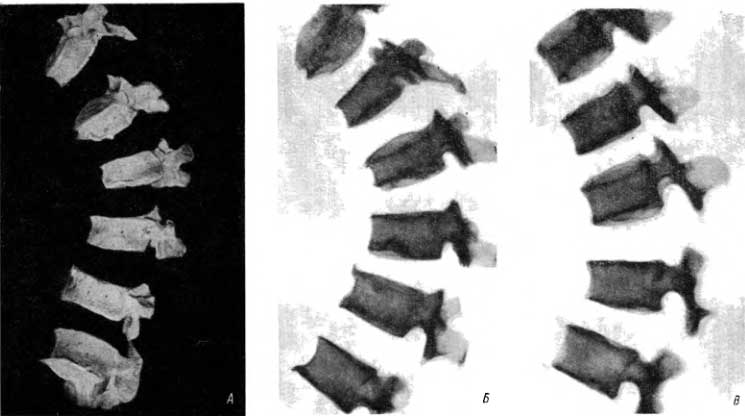

Это заболевание называют «юношеским кифозом» — kyphosis juvenilis seu adolescentium. Эти термины позволяют думать, что заболевание возникает у юношей, молодых людей. Указанными латинскими терминами (juvenis, adolescens) римляне пользовались для определения боеспособного мужского населения с 18 до 45 лет. Однако в 18 лет это заболевание позвоночника не начинается. К этому возрасту высота тела многих позвонков либо является окончательной, либо им предстоит увеличиться на 0.5, максимум на 1 мм. Разрушение хрящевой зоны роста в высоту (при повреждении верхней и нижней зон роста) максимум сказалось бы на указанную величину. При высоте тела грудного позвонка, равной 20 мм, уменьшение на 1 мм вряд ли бросается в глаза. Между тем при кифозе подростков высота переднего отдела тела пораженного позвонка меньше заднего отдела на 3–5 мм и больше (рис. 22, А и Б). Очевидно, что заболевание возникает не в юношеском возрасте, а раньше.

Рис. 22. А — кифоз подростков (позвоночник из погребения в Восточном Алтае, 1000 лет до и. о.); Б — рентгенограмма с позвонков; В — кифоз подростков, клиновидная деформация нижних грудных и I поясничного позвонка (IV–III в. до н. э.).

Некоторые называют это заболевание «остеохондропатическим кифозом». Каждая остеохондропатия характеризуется типичной сменой фаз и заканчивается восстановлением структуры спустя несколько лет. Восстановление, однако, не наступает при этом кифозе: рвы, ямы, обнаженная структура губчатого вещества тел поврежденных позвонков сохраняются навсегда (рис. 10, А и Б; 22, А, Б, В).

Некоторые называют данное заболевание «кифозом грудного отдела позвонков» (kyphosis dorsalis). Однако кифоз грудного отдела возникает и после компрессионного перелома одного и тем более двух позвонков. Кифоз грудного отдела обнаруживается (и иногда очень рано) при акромегалии. Следует также учесть, что кифоз подростков иногда связан с поражением не только грудных, но и верхних поясничных позвонков (рис. 22, В). Таким образом, и это название не является точным.